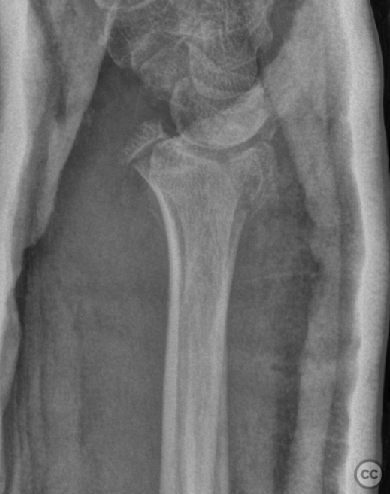

Multifragmentary Distal Radius Fracture with Flipped Ulnar Articular Margin

Clinical Details

Clinical and radiological findings:  A 72-year-old female sustained a multifragmentary, dorsally displaced distal radius fracture after a fall down stairs. Initial reduction revealed a 180-degree flipped fragment of the volar ulnar articular margin, unreducible by closed means. There was no mention of associated neurovascular compromise or open injury. Radiographs and intraoperative fluoroscopy confirmed the presence of a multifragmentary intra-articular fracture (AO/OTA 23-C3), with a flipped volar ulnar fragment and radial styloid impaction. The distal radioulnar joint alignment was restored postoperatively.